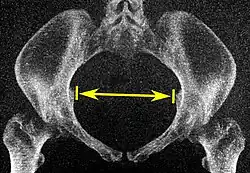

Low-dose 3D-rendered CT scans can be used for estimating the main pelvimetry parameters:[4]

| Parameter | Maximum intensity projections[5] | Thin slices | End points | Normal measures | |

|---|---|---|---|---|---|

| Pelvic inlet | Transverse diameter of the pelvic inlet |

|

Coronal plane |

The iliopectineal lines, at widest transverse distance. | 13 to 14.5 cm.[4] |